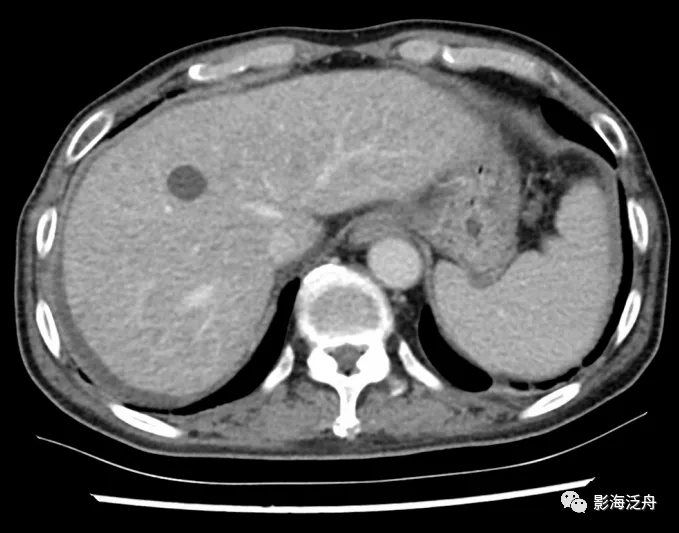

胰腺癌术后3月复查,肝周少量积液,增强门脉期肝实质密度略欠均匀,隐约